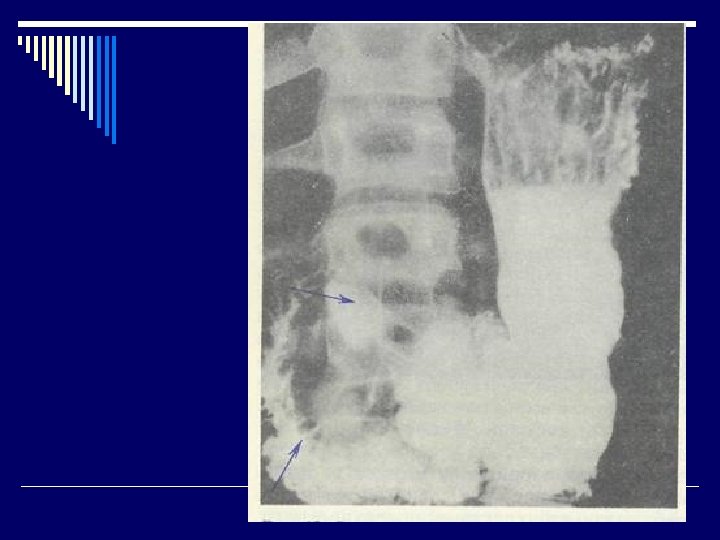

Инвазивные методы: быстрый уреазный тест, бактериоскопический, бактериологический, гистологический (“золотой стандарт”). Неинвазивные методы: - серологический; - дыхательный; - метод полимеразной цепной реакции - Интрагастральная р. Н-метрия - Рентгенологические исследования (по показаниям). - Ультразвуковое исследование органов брюшной полости.

Язва желудка (язвенная болезнь желудка) (Шифр R 25) Язва двенадцатиперстной кишки (язвенная болезнь двенадцатиперстной кишки) (Шифр R 26) o Язвенная болезнь (ulcus gasteris et duodeni) (пептическая язва)– хроническое рецидивирующее заболевание организма, которое характеризуется формированием язвенного дефекта слизистой оболочки желудка или двенадцатиперстной кишки, склонное к прогрессированию, сопроваждается болевым, диспепсическим, интоксикационным синдромами, нарушением секреторной и моторной функции желудка.

При обострении язвенной болезни обнаруживается язва, хронический активный гастрит, чаще – активный гастродуоденит, ассоциированные с Нр. В структуре гастроэнтерологических заболеваний язвенная болезнь составляет от 1, 7 до 16, 0 %. Чаще всего болеют подростки в возрасте 15 -17 лет. Чаще встречается язва 12 -типерстной кишки (8287 %), реже слизистой желудка (11 -13 %).